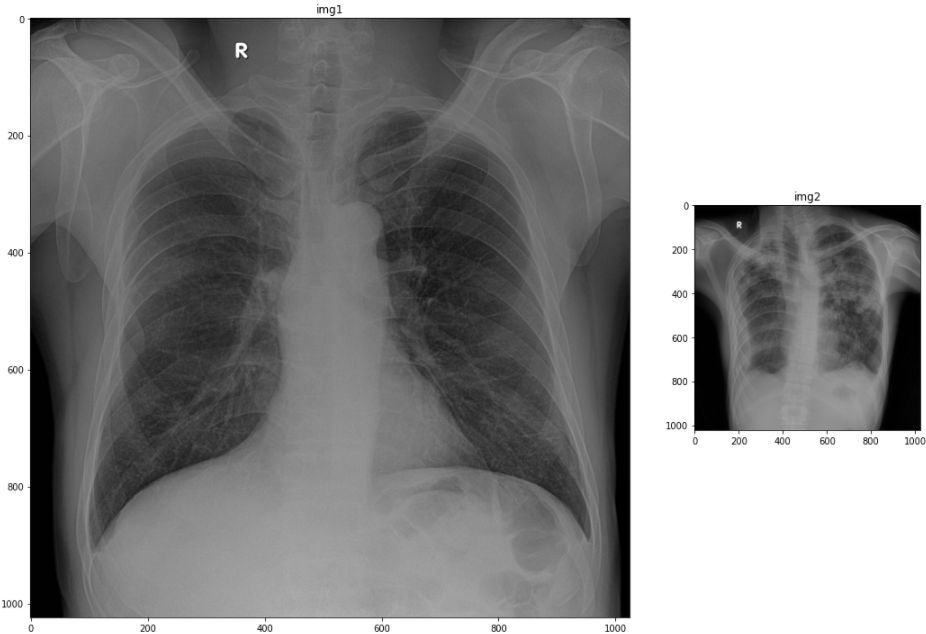

Figure range plot (pixel 범위, colorbar 띄우기)

plt.colorbar 이용

import matplotlib.pyplot as plt

fig = plt.figure()

rows = 1; cols = 2

ax1 = fig.add_subplot(rows, cols, 1)

ax1.set_title('img1')

image1 = ax1.imshow(img1, cmap='gray')

plt.colorbar(image1, fraction=0.046, pad=0.04)

ax2 = fig.add_subplot(rows, cols, 2)

ax2.set_title('img2')

image2 = ax2.imshow(img2, cmap='gray')

plt.colorbar(image2, fraction=0.046, pad=0.04)

fig.tight_layout()

plt.show()